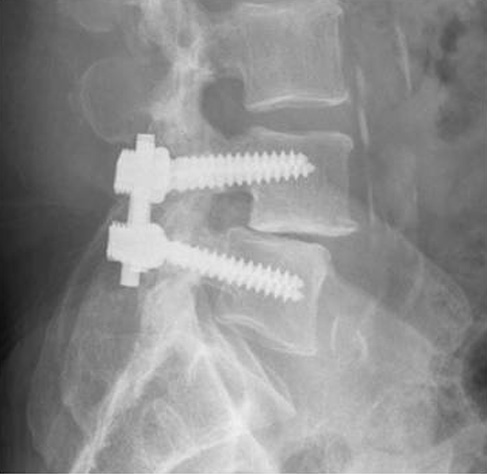

En esta radiografía de la fusión lumbar posterolateral (FLP), se han usado una varilla y tornillos para impedir el movimiento en los segmentos de la columna vertebral que se fusionan.